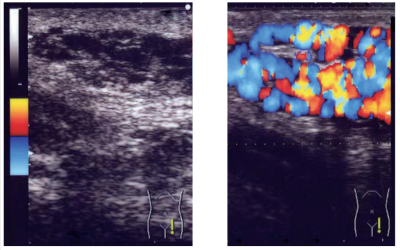

20 歳の男性。左陰囊の腫瘤を主訴に来院した。1 年前から陰囊上部の腫瘤に気付いていた。夕方になると時々左陰囊に鈍痛を自覚することがあった。立位での左陰囊上部の写真を別に示す。破線で囲まれた部位に腫瘤を触知する。腫瘤は柔らかく、仰臥位で縮小し立位で腹圧を加えると腫大する。臥位での破線部の安静時超音波像と腹圧時カラードプラ超音波像を別に示す。